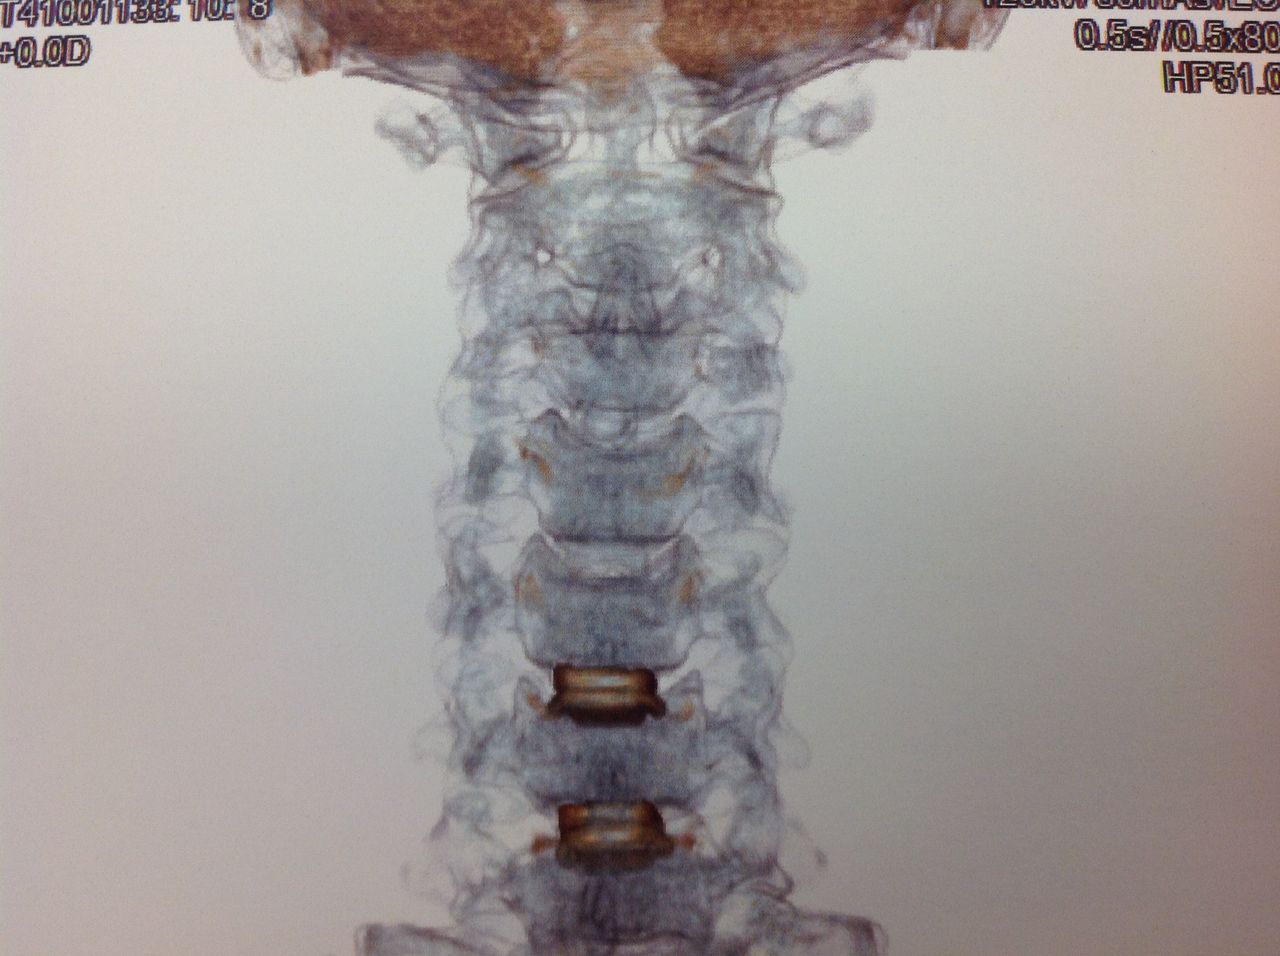

Como especialista em Neurocirurgia faço tratamentos de doenças relacionadas ao Sistema Nervoso Central como tumores, patologias vasculares, traumatismo e Infecções que necessitem de uma abordagem cirúrgica ou acompanhamento Clínico.

Sou especialista em Cirurgia da Coluna Vertebral e Medicina da Dor em que faço tanto tratamentos clínicos quanto cirúrgico.

• Cirurgia da Coluna Cervical

• Cirurgia da Coluna Lombar

• Cirurgia endoscópica da coluna

• Doenças Da Coluna Vertebral

• Fraturas Da Coluna Vertebral

• Cirurgia da coluna vertebral

• Cirurgia minimamente invasiva da coluna vertebral